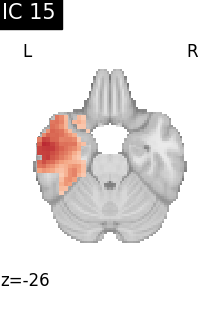

Finally, we plot the map for each ICA component separately

for i, cur_img in enumerate(iter_img(canica_components_img)):

plot_stat_map(

cur_img,

display_mode="z",

title=f"IC {int(i)}",

cut_coords=1,

vmax=0.05,

vmin=-0.05,

colorbar=False,

)

show()